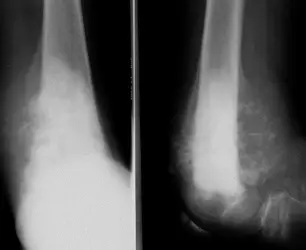

| Compartment Syndrome | Increased pressure within a closed fascial compartment, leading to reduced tissue perfusion, hypoxia, and irreversible muscle and nerve damage. Causes: Fractures (especially tibia/forearm), severe soft tissue trauma, arterial injury, burns, tight casts/dressings, post-ischemic reperfusion swelling, IV fluid extravasation, and bleeding disorders (e.g., hemophilia). High-Risk Notes: Pain may be absent in altered consciousness, children (monitor analgesia response), polytrauma, sedated/epidural cases, or concomitant nerve damage. Open fractures do not always decompress pressure. Gross/Clinical: -tense, shiny leg swelling with blisters in compartment syndrome.Imaging: - Intraoperative fasciotomy | History/Symptoms: Pain out of proportion to the injury (e.g., a “bursting” sensation), which is not relieved by analgesia. Clinical Features (The 5 P’s): - Pain with passive stretch (early, key sign; e.g., ankle dorsiflexion for leg, wrist for forearm). - Paresthesia (early). - Palpable tense swelling (shiny skin, blisters: clear=mild, serosanguinous=severe, bloody=worst; dusky/pallor skin). - Pallor, Paralysis, Pulselessness (late, ominous signs; pulses often palpable until late). Investigations: Primarily a clinical diagnosis (high suspicion key). Compartment pressure measurement can confirm: absolute pressure >30 mmHg or Delta Pressure (Diastolic BP - Compartment P) ≤ 25 mmHg. | Initial: ABCs, supplemental oxygen. Remove all circumferential dressings, casts (bivalve to skin), and splints. Elevate the limb to heart level (not above; higher reduces inflow). Correct any hypotension. Surgical: Urgent Fasciotomy if no response within 1h or confirmed pressure (prophylactic in high-risk like major osteotomy). Release all compartments/skin with long incisions; debride necrotic muscle via 4C’s (early: pink/red, soft, contracts/bleeds on pinch; late: dark, firm, no response); preserve neurovascular. Wound open (bulky dressing/splint, VAC, or boot-lace gradual closure); repeated inspections x48h; coverage in 3-5 days (skin graft usual; flap if nerves/vessels/bone exposed). | Cellulitis, Deep Vein Thrombosis (DVT), Arterial occlusion, Severe soft tissue injury without compartment syndrome; equivocal cases in polytrauma. | Complications: Volkmann’s ischemic contracture (permanent deformity, weakness, sensory loss, chronic pain). Contraindications (Fasciotomy): Confirmed >48h (irreversible damage, high infection risk from dead tissue); crush injuries with already necrotic muscle. |

| Open Fracture | A fracture with a breach in the overlying skin and soft tissues, creating communication with the external environment. All open fractures are considered contaminated (even small punctures; aka compound fracture). Causes: Can result from high-energy trauma (RTAs, falls, firearms; signs: degloving, crush syndrome, bone loss, segmental) or low-energy trauma. Contamination risk higher with farm/soil injuries, bites, delayed presentation (>12h), fecal/oral/soil/water exposure. Mechanism: Low/high velocity missiles (cavitation >300 m/s); in-out (cleaner) vs. out-in (dirtier). Gross/Clinical: ![]() | History: Mechanism of injury (energy, time, place, type/impact method), consciousness, wound size/bleeding amount, other injuries (often missed), tetanus status. Assessment: ATLS protocol (ABCDE) first (treat patient, not fracture; exclude shock/brain injury, monitor vitals; viscera exam: ribs=lungs/liver/spleen, pelvis=bladder/urethra). Examine wound (look/feel/move carefully post-splint), check distal neurovascular status, compartment syndrome. Photograph/remove gross contamination; cover with saline dressing. Classification (Gustilo-Anderson): - Type I: <1 cm wound, clean, minimal soft tissue. - Type II: >1 cm wound, moderate soft tissue (no stripping). - Type IIIA: Extensive soft tissue damage, but adequate bone coverage. - Type IIIB: Extensive soft tissue loss with periosteal stripping; bone exposed, requires flap coverage. - Type IIIC: Any open fracture with an arterial injury requiring repair. | Initial (ER): ATLS first. Cover wound with sterile saline-soaked dressing, splint limb, IV fluids (request blood if needed); traction if no distal pulse/deformity. Prophylaxis: Tetanus prophylaxis/serum and broad-spectrum IV antibiotics immediately (culture tissue/blood); clean major contamination. Surgical: Urgent debridement/irrigation within 6-12h (“Dilution is the solution to pollution”; pulse-irrigate 3-6-9L saline; excise non-viable tissue/foreign material, trim skin edges, remove dead muscle/detached bone, preserve N/V). Stabilization: external fixator (preferred severe; replace with cast post-infection); internal if clean/minimal. Wound closure delayed (primary if small/clean; secondary if contaminated/large). Early soft tissue cover. | The diagnosis is typically obvious. Key: Classify severity; identify associated injuries like compartment syndrome, vascular damage, or high-energy signs (e.g., crush). Differentials for contamination: Primary (field debris) vs. secondary (post-fixation if poor debridement). | Complications: Infection (cellulitis, osteomyelitis, chronic with sequestra/drainage, gas gangrene), tetanus; higher with delay/exposure/bites. - embolisms fat, thrombi others.. Case Insight: Unconscious patient (e.g., open tibia post-RTA): ABCDE/cervical collar, distal pulses/traction, admit for debridement; ankle fall: Splint post-ABC, assess neurovascular. |